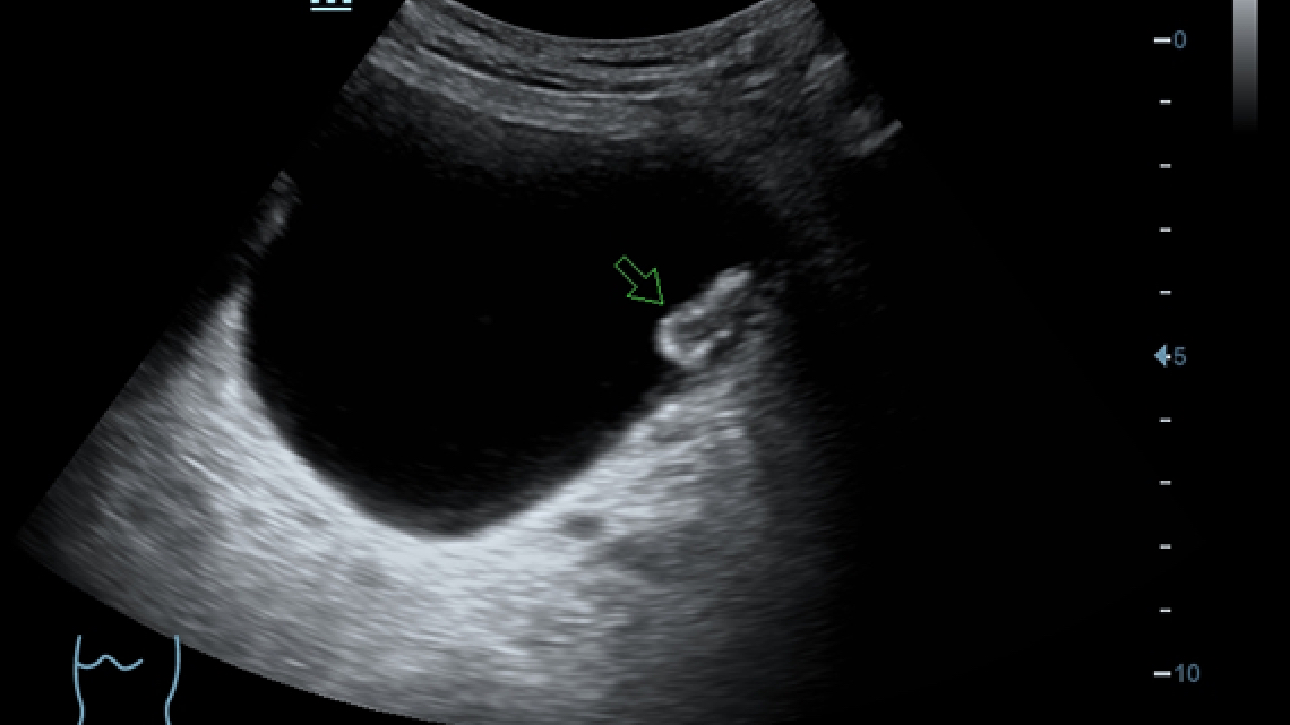

Klinische Bilder